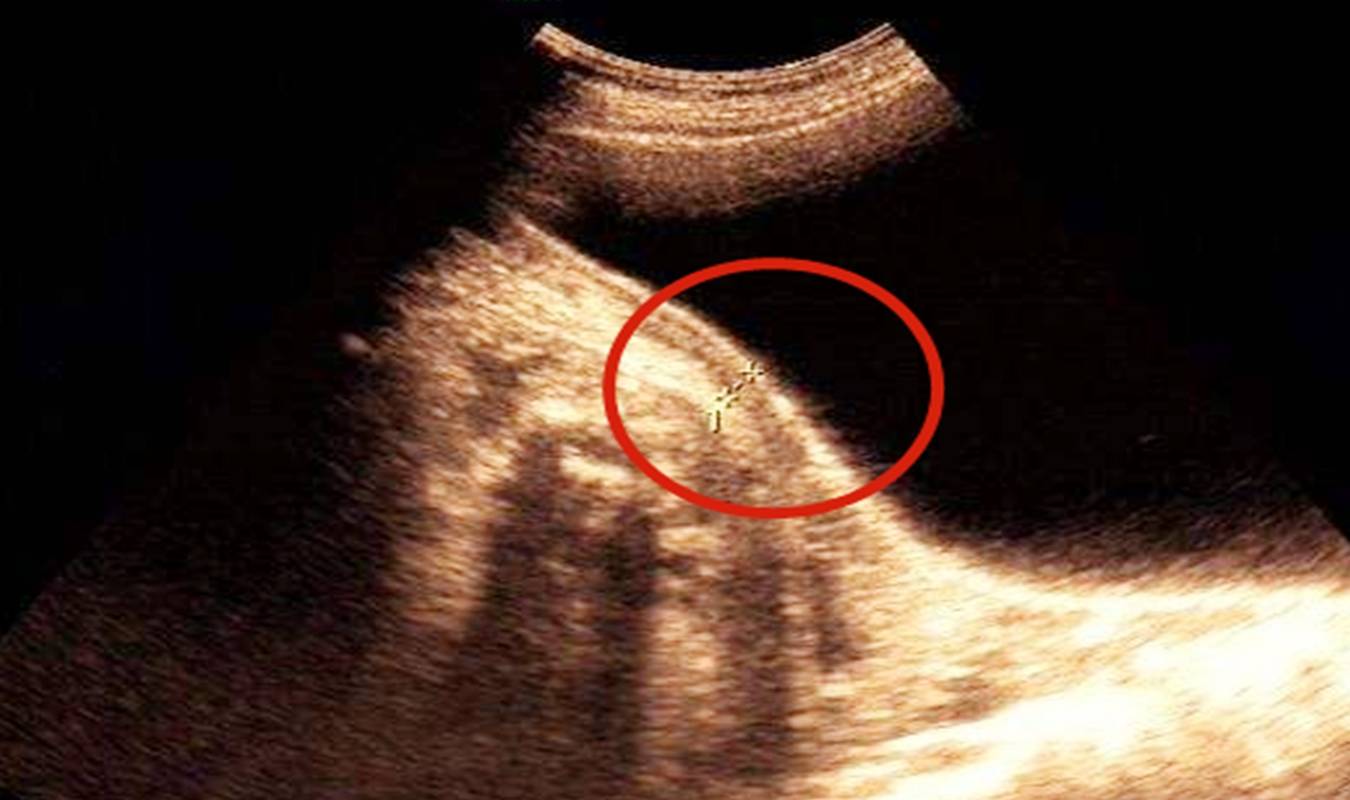

1) 子宫瘢痕的评估

经历过剖腹产的产妇 , 除了在肚子上留有一道疤痕之外 , 子宫上也会有一道切口疤痕 。

如果下一胎想要顺产 , 这个子宫上的疤痕就成为一个重要的影响因素 。 子宫疤痕厚度会直接影响是否可以顺产 。

一般来说 , 疤痕厚度≥4毫米 , 才可以考虑顺产 , 如果疤痕过薄 , 很容易在宫缩的时候 , 子宫出现破裂 。

所以想要二胎顺产的孕妇 , 子宫疤痕是不能忽视的因素 。